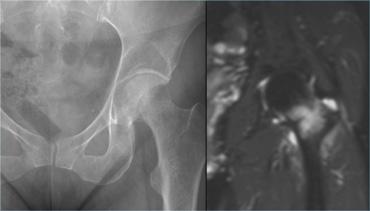

Có hai loại gãy xương do stress ở cổ xương đùi:

- Gãy xương do lực nén. Loại này nằm ở mặt trong của cổ xương đùi.

Nguy cơ liền xương phức tạp thấp khi điều trị bảo tồn, do các mảnh gãy được ép chặt vào nhau. - Gãy xương do lực căng. Loại này nằm ở mặt ngoài của cổ xương đùi.

Nguy cơ liền xương phức tạp cao

do lực căng tác động lên các mảnh gãy.

Loại gãy này có nguy cơ tiến triển thành gãy xương hoàn toàn và hoại tử vô mạch.

Nếu điều trị bảo tồn thất bại, nên chỉ định nắn chỉnh hở và cố định bên trong.

Hình bên trái cho thấy gãy xương do lực nén ở cổ xương đùi.

Hình X-quang bình thường, nhưng MRI phát hiện đường gãy và phù tủy xương (tức là độ 4).

Hình X-quang chụp một tháng sau cho thấy tổn thương tiến triển thành gãy xương hoàn toàn.

Mặc dù đây là loại gãy xương nguy cơ thấp, các hình X-quang theo dõi tại thời điểm 3 và 13 tháng vẫn cho thấy xu hướng liền xương kém.